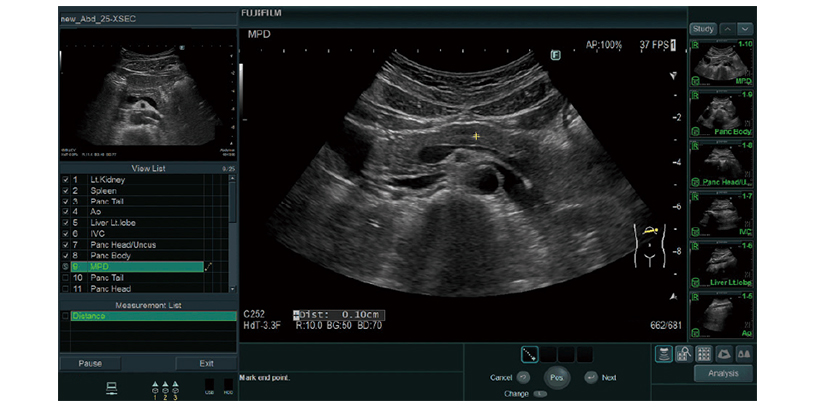

Protokol Asistanı

Önceki sabit muayene protokolleri ve görüntüleme koşulları kaydedilebilir. Düğme işlemleri, muayenelerin etkinliğini desteklemek için önemli ölçüde azaltılabilir. Ek olarak, “Kılavuz Görünümü” işlevi aracılığıyla bir referans görüntü görüntülenebilir.